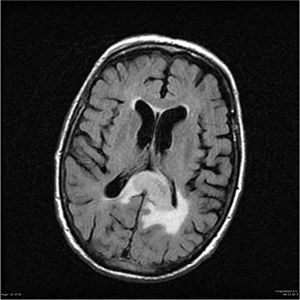

Astrocytes are star-shaped brain cells located between nerve cells. When they start dividing without control, they create a tumor called astrocytoma. These tumors come in different grades – low grade tumors are slow-growing while high-grade tumors can be very aggressive.